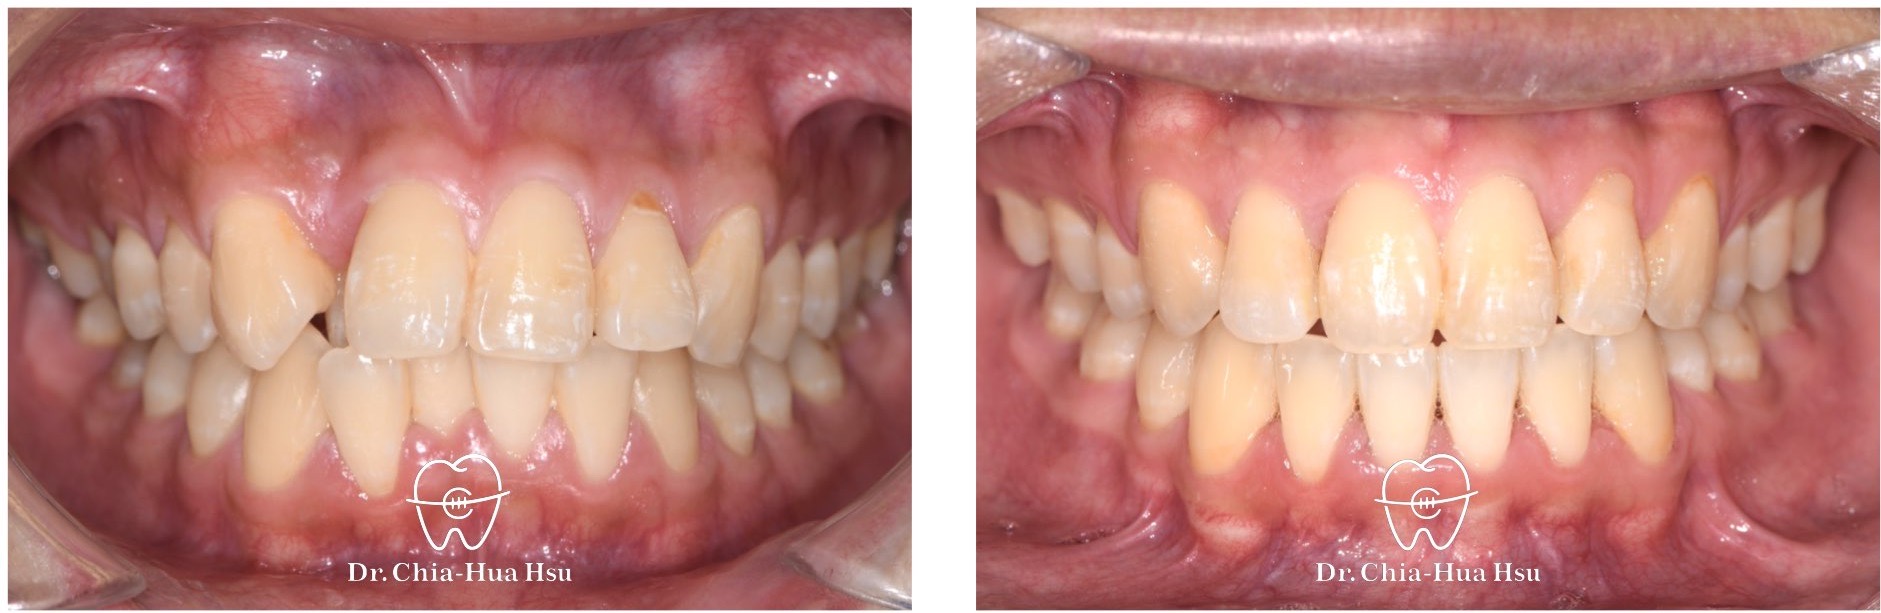

- 治療結果:齒列排齊,嘴凸也有顯著改善,甚至下巴輪廓更明顯。

治療前

治療後